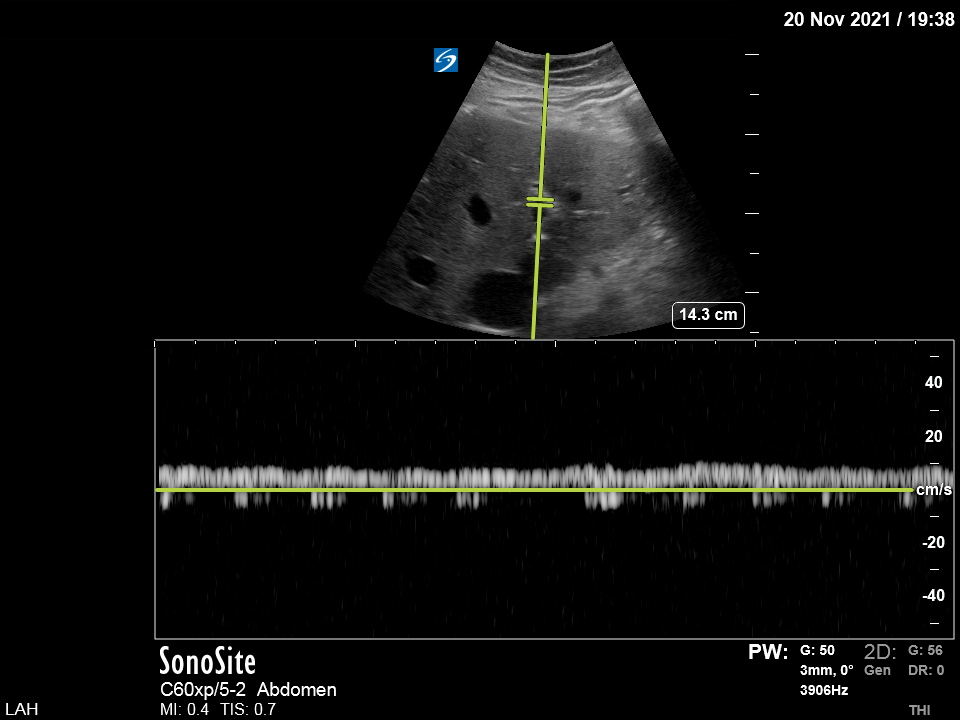

I looked at the portal vein and - to my surprise - there was no pulsatile flow: